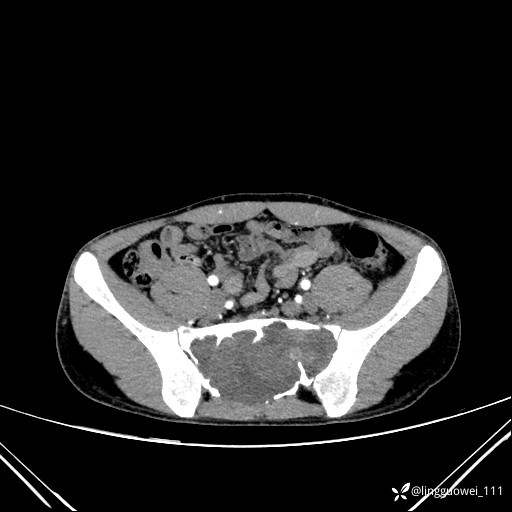

男,25岁,腰痛4年,加重左下肢痛5天,先上传X光片,第2天再上传CT。MR

动脉期:

静脉期: